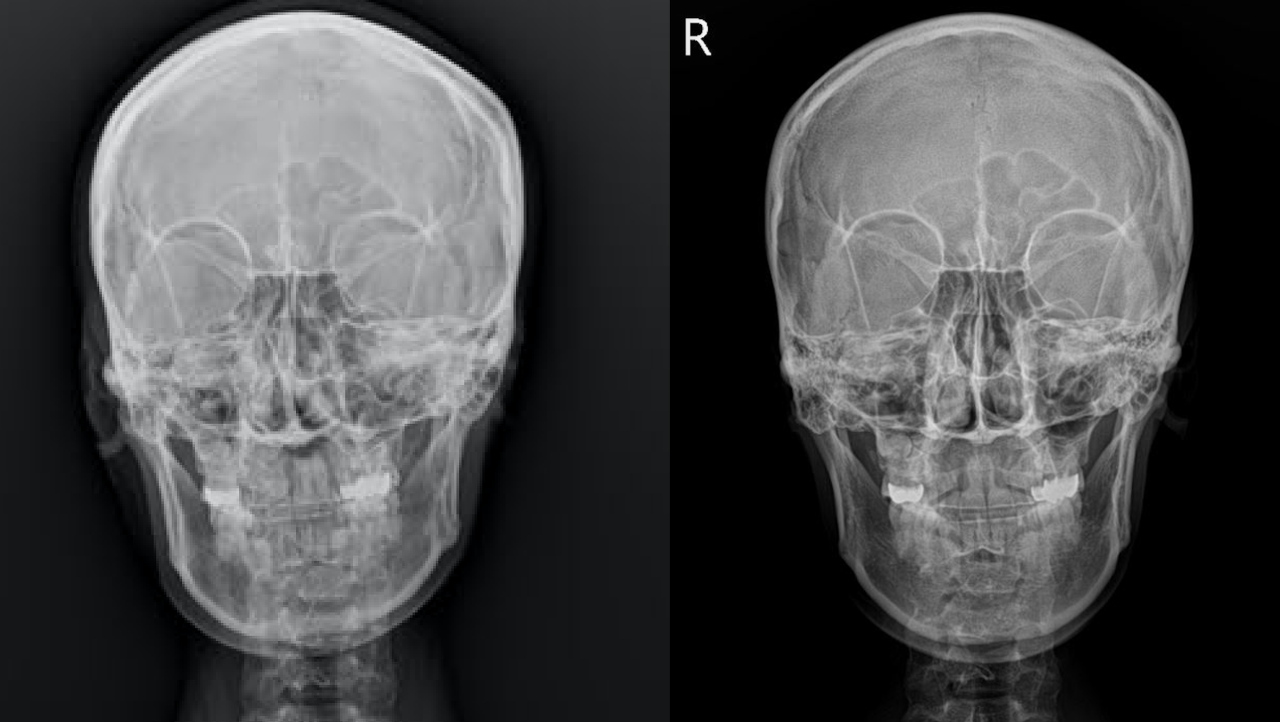

air는 엑스레이에서 까맣게 보여요

위 사진의 두 환자 분의 경우 두개안면골의 비틀림을 재정렬해주는 것만으로도 비중격이 위치가 개선되고 비강 내 공기의 흐름이 좋아진 것을 관찰할 수 있습니다.